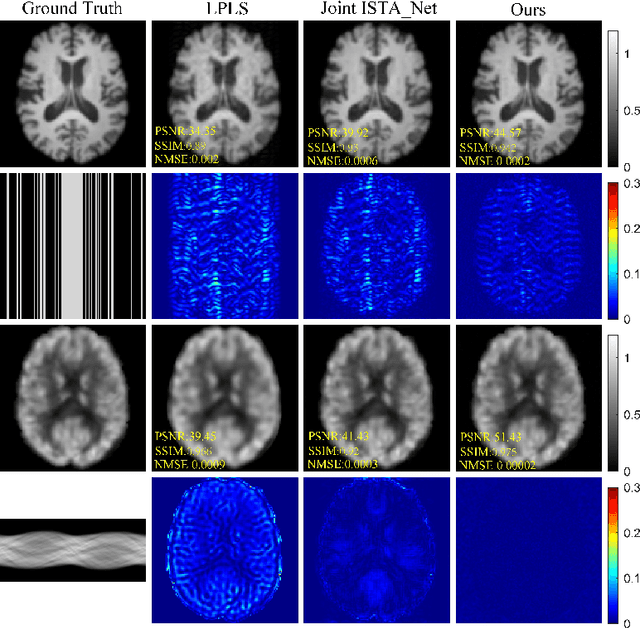

Abstract:Positron Emission Tomography and Magnetic Resonance Imaging (PET-MRI) systems can obtain functional and anatomical scans. PET suffers from a low signal-to-noise ratio. Meanwhile, the k-space data acquisition process in MRI is time-consuming. The study aims to accelerate MRI and enhance PET image quality. Conventional approaches involve the separate reconstruction of each modality within PET-MRI systems. However, there exists complementary information among multi-modal images. The complementary information can contribute to image reconstruction. In this study, we propose a novel PET-MRI joint reconstruction model employing a mutual consistency-driven diffusion mode, namely MC-Diffusion. MC-Diffusion learns the joint probability distribution of PET and MRI for utilizing complementary information. We conducted a series of contrast experiments about LPLS, Joint ISAT-net and MC-Diffusion by the ADNI dataset. The results underscore the qualitative and quantitative improvements achieved by MC-Diffusion, surpassing the state-of-the-art method.